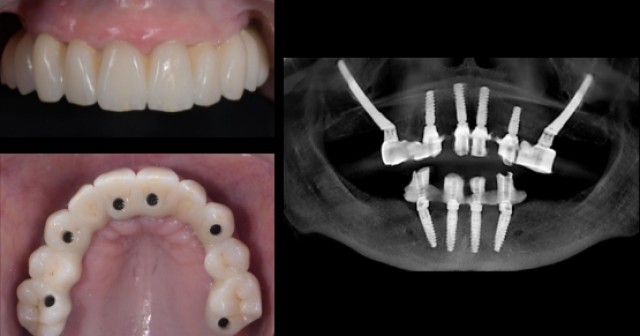

Zygomatic Implants vs. Bone Grafting for Full-Arch Solutions

Dr. Ricardo Mitrani explores the benefits of zygomatic implants vs. bone grafting as a safe and efficient solution for full…By Ricardo Mitrani